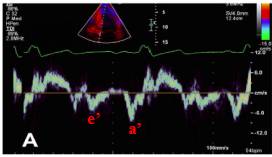

11、肺静脉血流频谱指标

●肺静脉血流频谱:S峰、D峰、S/D比值及Ar峰

●在LVEF小于40%时,与LA顺应性减低与LA平均压增高、增加有关

12、三尖瓣收缩期返流峰值流速—TR

●PA压力增高:TR压差+RA压

●PA平均压的准确评估